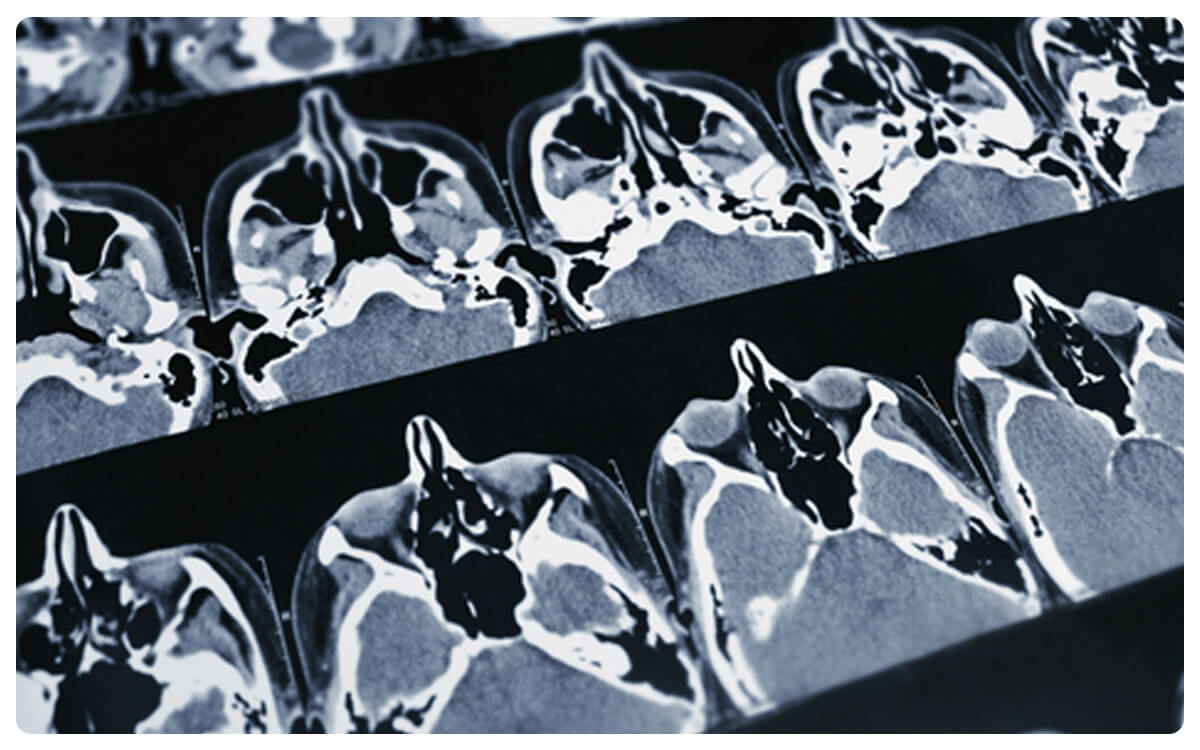

La Tomografía Toracoabdominal, una técnica avanzada de imagen médica, se presenta como una herramienta esencial en la evaluación integral y detallada de las estructuras anatómicas en la región del tórax y el abdomen. A través de la tomografía computarizada y, en ocasiones, la administración de un medio de contraste intravenoso, esta técnica permite la obtención de imágenes tridimensionales de alta resolución que brindan una visión completa de órganos, tejidos y posibles afecciones en estas áreas.

La Tomografía Toracoabdominal desempeña un papel crucial en el diagnóstico y seguimiento de enfermedades y patologías en ambas regiones, proporcionando información valiosa para la detección temprana de anomalías y la toma de decisiones clínicas informadas en el cuidado integral de la salud.